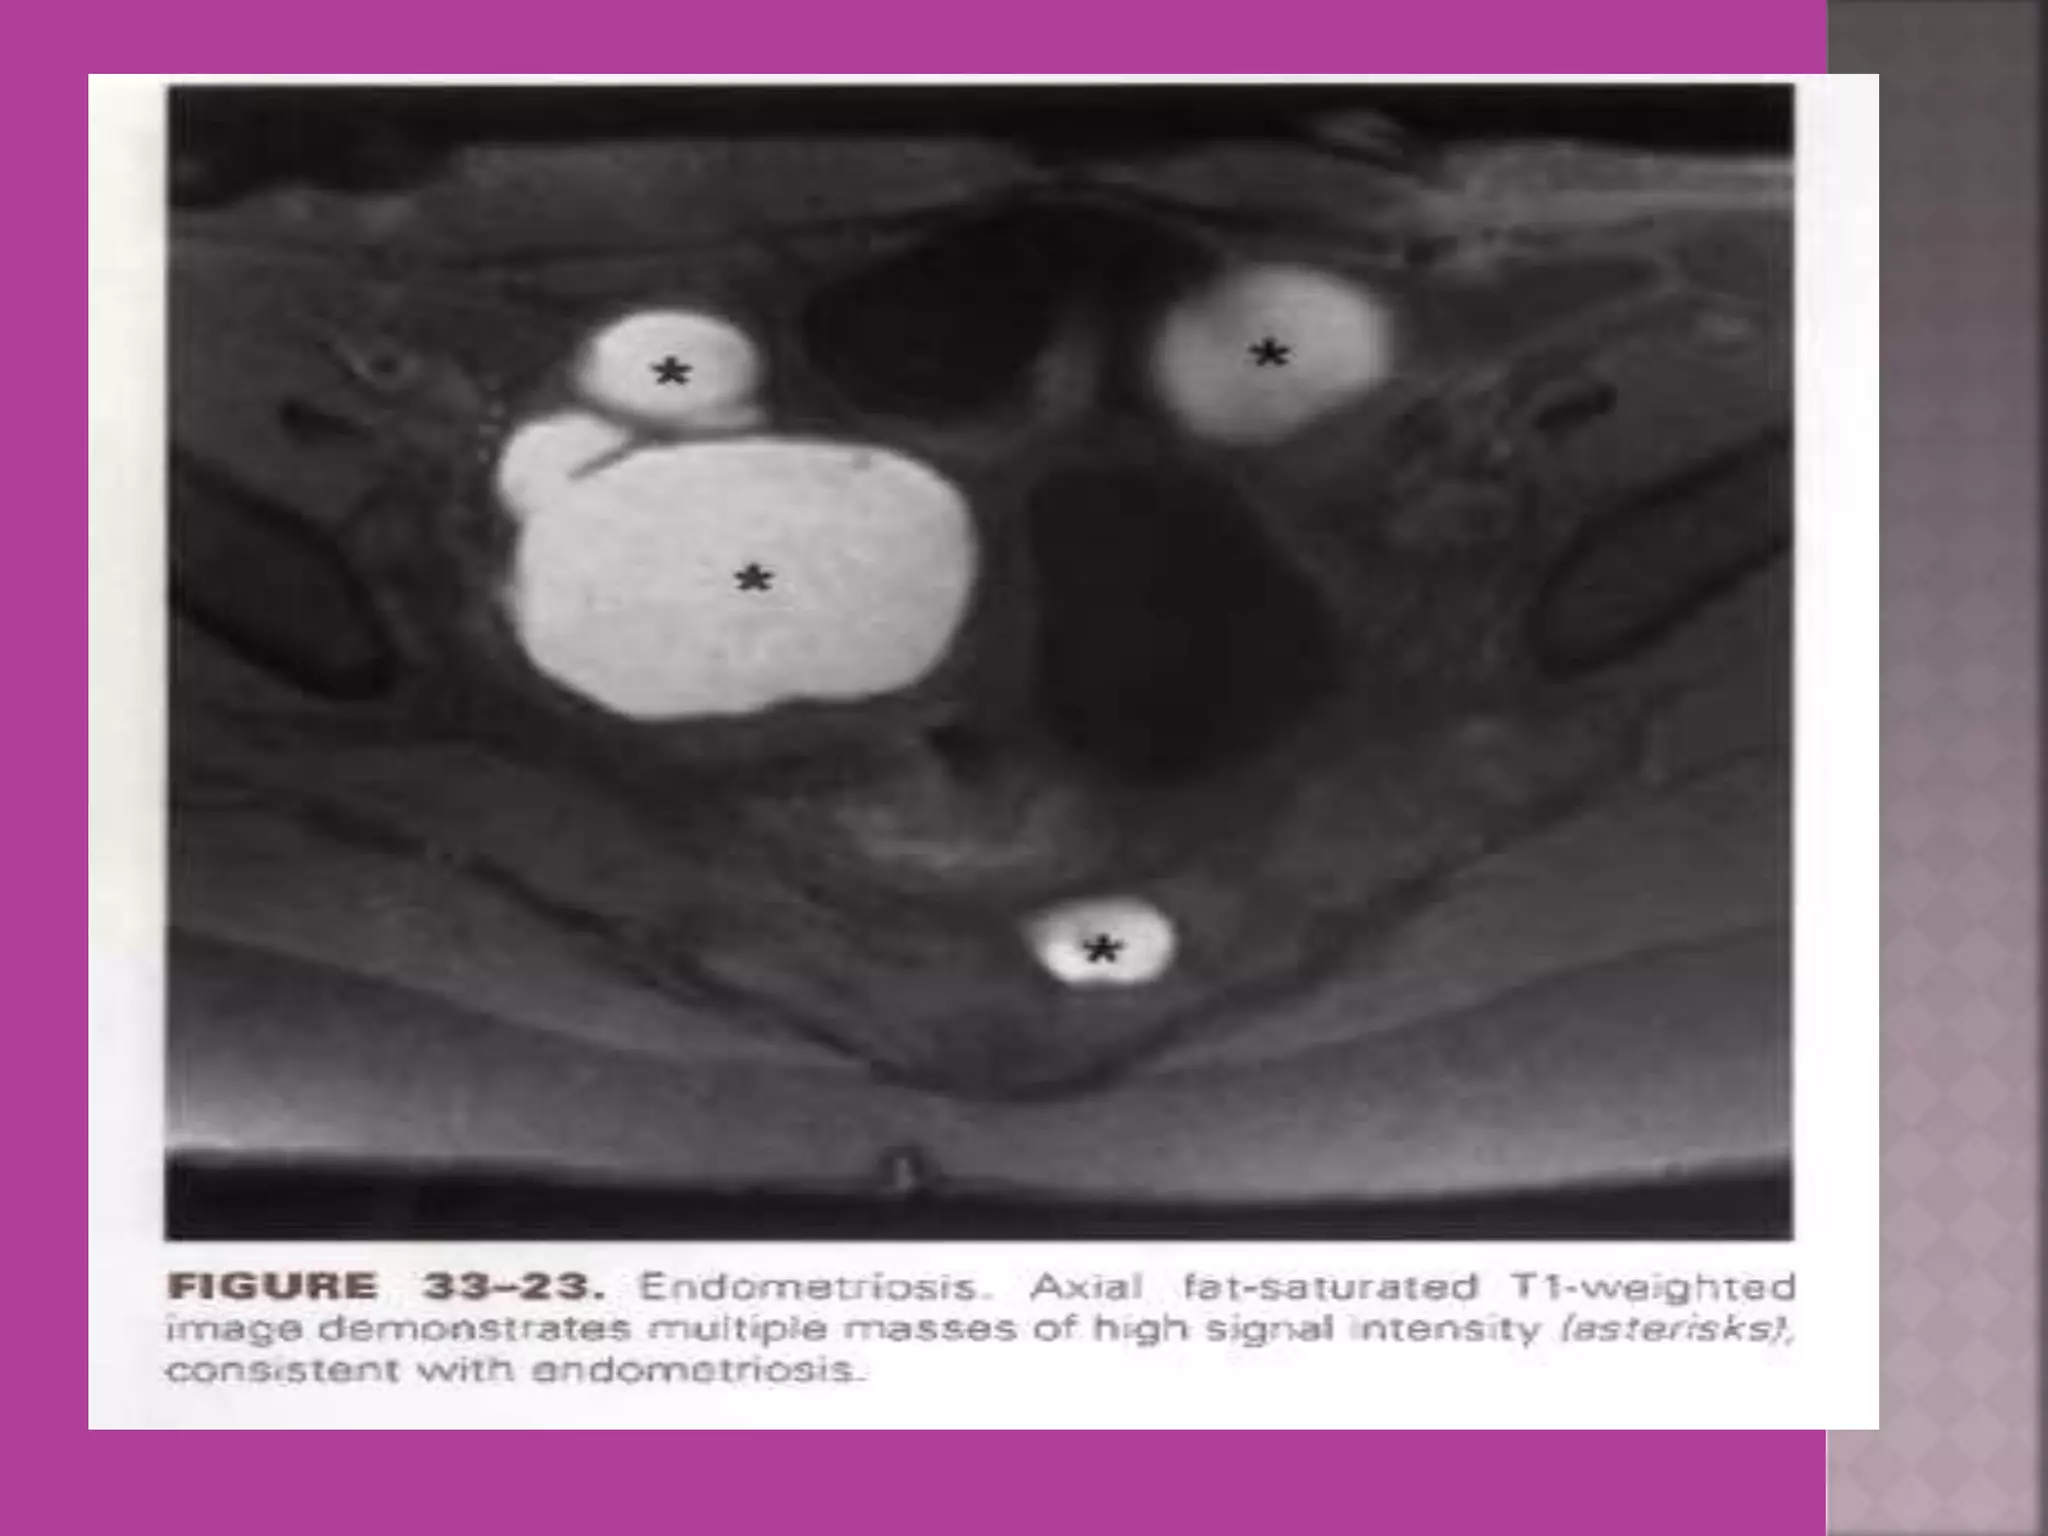

Ovarian Endometriomaa

 MRI ismost sensitive for diagnosis of Adenomyosis.  MRI Is more accurate and informative in diagnosis of congenital malformation of genito-urinary tract.  Retroparitoneal lymph node > 1cm can be identified so also such small deposits on bowel / bladder liver can be identified in cases of cancers.  It is more sensitive and accurate tool to assess infiltration of myometrial/ cervical wall, adjoining organs and parametrium --thus helps in pre operative staging of genital carcinomas.  As it is safe in pregnancy –it is useful in diagnosis of obstetrical conditions as well s differentiation of tumors (benign / malignant ) complicating pregnancy.